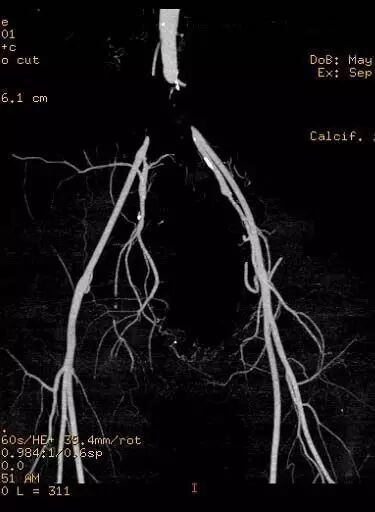

“问题找到了,是你的双侧髂动脉堵塞,你看看,在你下腹部的位置,这样下肢供血不足,从而影响到两条腿的活动和生殖系统的功能。”周主任指着检查报告说。